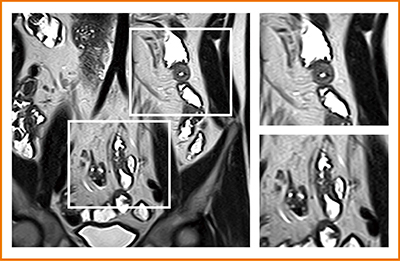

図3は,同日に大腸内視鏡のみを行った症例で,大腸には異常は認められなかったためフォローとなったが,MRIでは空腸と近位回腸に壁肥厚と浮腫が認められ,造影T1強調画像でも増強効果の亢進が見られたことから,空腸の病変を指摘することができた。

図3 MRIで空腸,近位回腸に病変を指摘できた例